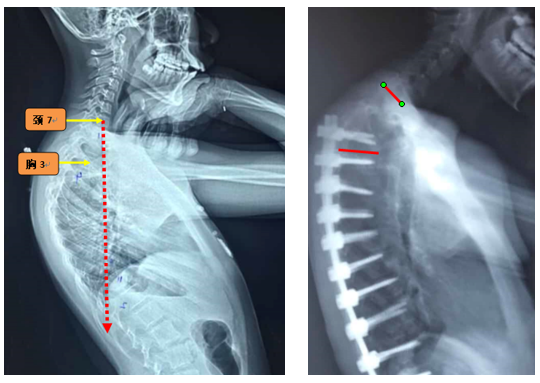

Ø 颈7铅垂线距离UIV太远

图19 颈7铅垂线距离UIV太远

Ø 上固定椎在上终椎的尾端

图20 Lenke 1型脊柱侧弯上固定椎(UIV)选择在上端椎(UEV)的尾端是导致PJK的危险因素